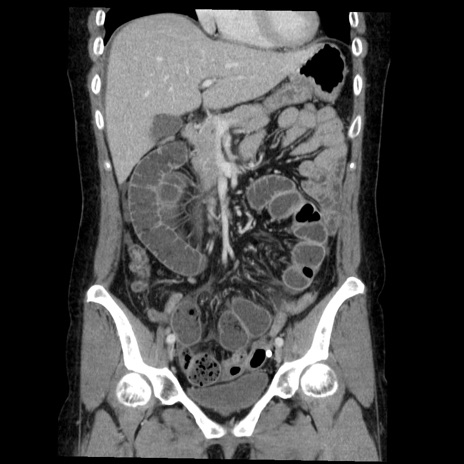

症例6(冠状断像)

【症例】50歳代女性

【主訴】下腹部痛

【現病歴】本日朝より下痢2回あり。 昼食を食べた後、嘔吐3回、下腹部痛認め、症状軽快せず、当院救急搬送。

最終食事:本日昼(生ものなし)。 昨日の夜、刺身を食ぺたとのこと。周囲に同様の症状の者なし。普段、排便は毎日あるとのこと。

【既往歴】卵巣癌術後(8年前に当院で卵巣摘出)

【身体所見】 意識清明、腹部:平坦、腸蠕動音→、やや硬、下腹部自発痛・圧痛あり、反跳痛あり、筋性防御なし。

【データ】WBC 16000、CRP 0.01